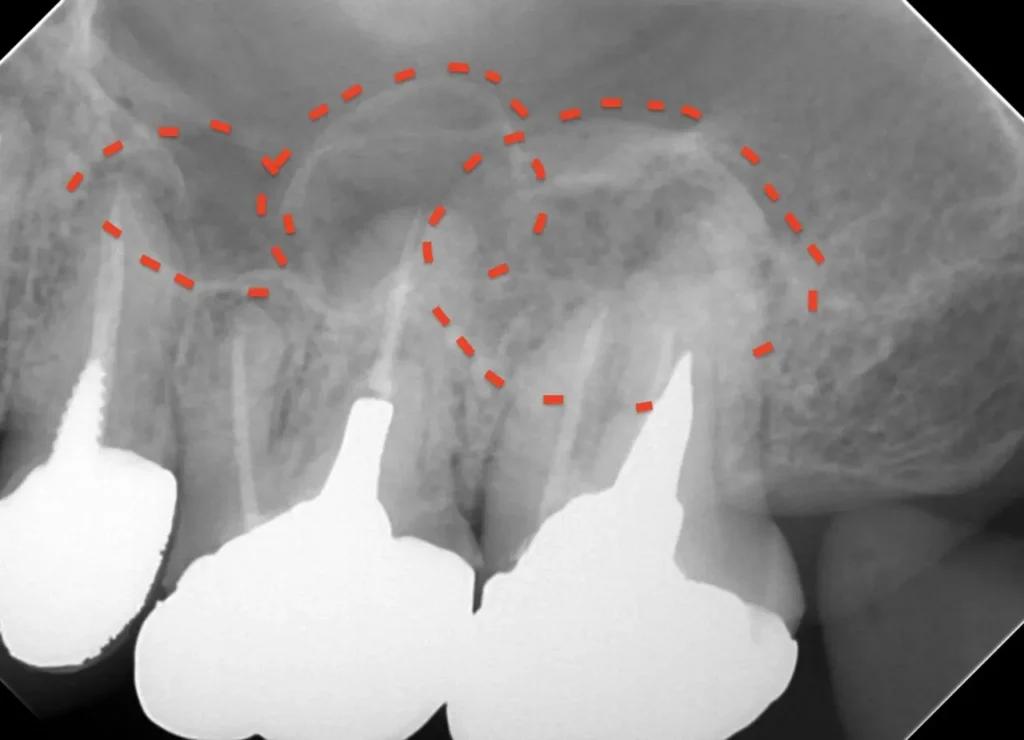

CT画像

副鼻腔の骨の壁を突き破っています

術後3年CT画像

骨の穴は完全に消えました